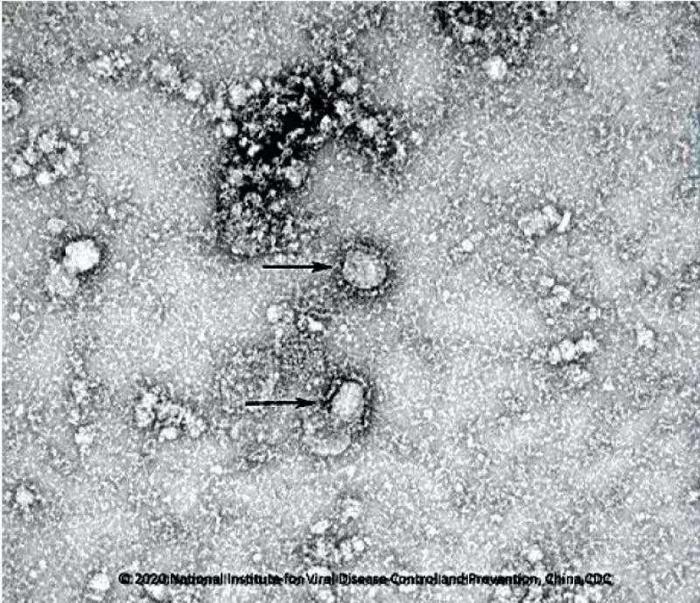

图片来源:中国疾控中心网站

中新网1月24日电 据中国疾控中心网站消息,为做好新型冠状病毒感染的肺炎疫情防控支撑工作,发挥国家病原微生物资源库科技资源共享服务职能,国家病原微生物资源库于1月24日发布了由中国疾病预防控制中心病毒病预防控制所成功分离的我国第一株病毒毒种信息及其电镜照片、新型冠状病毒核酸检测引物和探针序列等国内首次发布的重要权威信息,并提供共享服务。